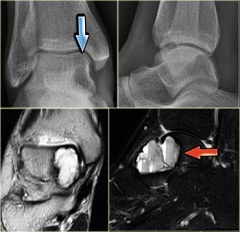

Голеностопный сустав представляет собой сочленение стопы и костей голени (таранной, малоберцовой и большеберцовой костей). Киста голеностопного сустава отличается меньшими размерами, формирование ее также протекает бессимптомно, локализуется на тыльной стороне сустава. Киста голеностопного сустава также является следствием дегенеративных процессов сустава, травм.

Коленный сустав – суставный комплекс, соединяющий большеберцовую и бедренную кости, а также коленную чашечку (надколенник). Киста коленного сустава формируется на его тыльной стороне. Сформировавшаяся киста локализуется в подколенной ямке. Киста коленного сустава также называется кистой Беккера.

Основным риском при диагностировании кисты коленного сустава является ее разрыв с излиянием содержимого в близлежащие ткани, что может спровоцировать воспалительный процесс в тканях. Киста коленного сустава в большинстве случаев обусловлена частыми травмами.